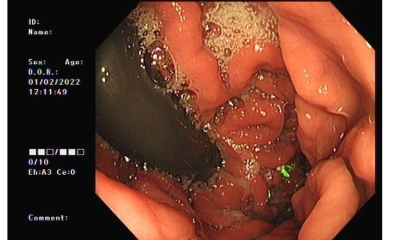

sadly with the Case locally the patient is labelled delusional as it's not visible on imaging. I've included endoscopic image showing it and the professor of gastroenterology states it's food, I've included a 50p I've soaked in HCl and this has developed a patina, it's oxidised and on green. Which is what's happened to the coin in the fundus, that's dismissed as food.

I have consulted an associate who is a prominent gastroenterologist and he himself has doubts that a two-year-old would pass the coin. This is due to the size and most gastroenterologists are blatantly told that anything over 20 mm is very unlikely to leave the stomach and this would be for the reasons I highlighted previously. Unless you have physically seen the coin with your own eyes in the child's feces. An x-ray will not be conclusive for the reasons I have highlighted, the way you'll be able to check is if your child or the person who has ingested the coin, develops psoriasis, as the released nickel is known to cause this, furthermore they will develop issues with their lymphatic system because the nickel migrates to the lymphatic drainage system where it will cause pastels around the lymph nodes, swelling of the lymph nodes and cutaneous lesions around them. You'll also find green scaly skin probably around the elbows which is a high maintenance area and as a result seems to attract the accumulation of the nickel components, if you apply dermal 500 lotion to this scaly material and scrape it off after a few mins you will end up with a green cream. See attached images, I have actually included an image of regurgitated fluid from the affected individual stomach the clear stuff is gastric fluid and the other staff is blood caused by bleeding and the circle patch is a section of the gastric mucosus which has been cut out by the coin pictures of the coin institute, I have also included the fundus image, showing the coin buried in the gastric mucosa and the little cut out which was circled in one of the attached pictures.